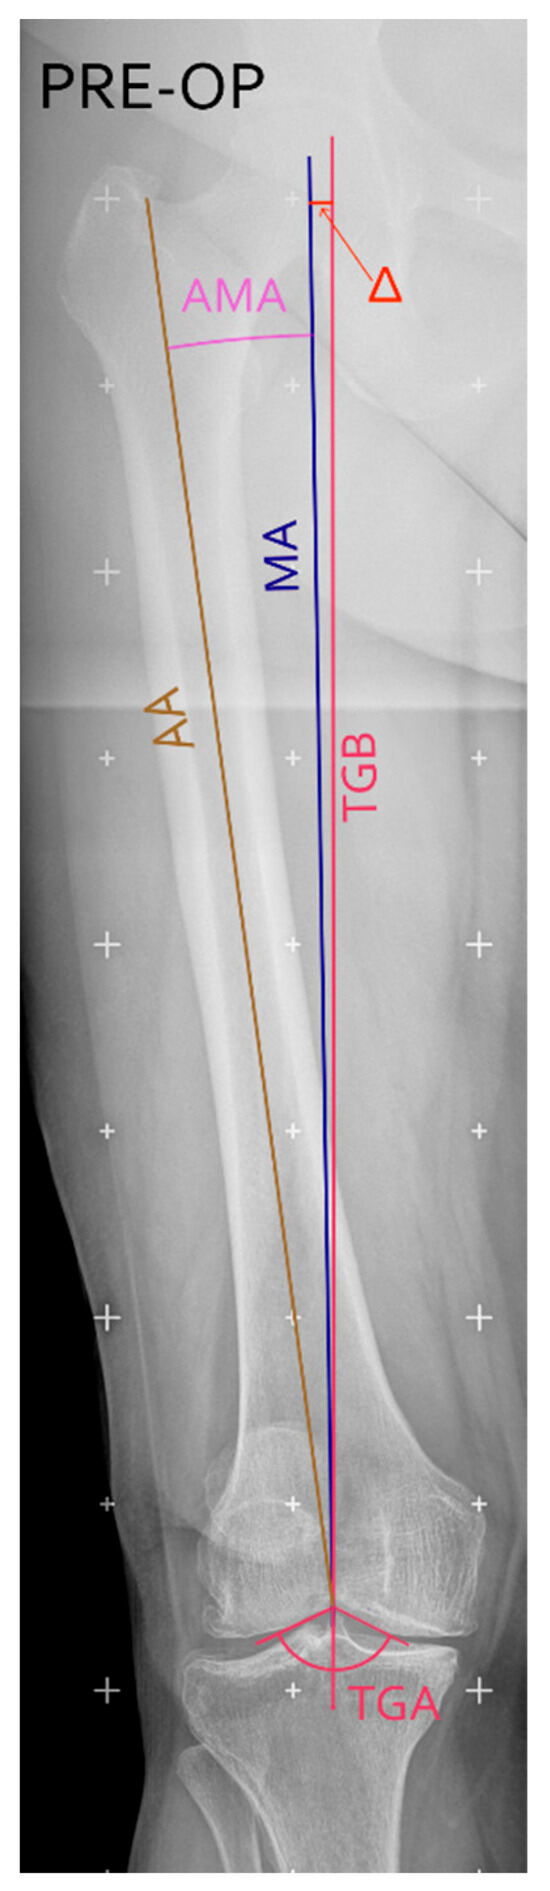

Background/Objectives: This study introduces and evaluates a novel surgical technique for total knee arthroplasty (TKA) that uses the trochlear groove bisector (TGB) as an anatomical landmark to achieve kinematic alignment of the femoral component in the coronal plane. The aim of the [...] Read more.

Background/Objectives: This study introduces and evaluates a novel surgical technique for total knee arthroplasty (TKA) that uses the trochlear groove bisector (TGB) as an anatomical landmark to achieve kinematic alignment of the femoral component in the coronal plane. The aim of the present retrospective observational analysis was to assess the reproducibility and accuracy of this approach and to report preliminary clinical outcomes. Methods: Twenty-eight TKA procedures were performed using the TGB-guided alignment technique. Preoperative planning and postoperative assessments were conducted on long-leg weight-bearing radiographs to measure the agreement between planned and achieved alignment, analysed using Bland–Altman statistics. Functional outcomes were evaluated at 12 months with the Knee Society Score (KSS), Forgotten Joint Score (FJS), and patient satisfaction. Results: The mean difference between planned and post-operative mLDFA was −0.3° ± 0.65°, with a root mean square error (RMSE) of 0.7°, demonstrating high accuracy and reproducibility. Postoperative outcomes showed mean KSS (knee = 89.6, function = 91.4), FJS = 69.6 ± 12, mean flexion = 124.6°, and mean HKA = 178°. Ninety percent of patients reported being satisfied or very satisfied at 12 months. Conclusions: The TGB-based technique offers a reliable, easily applicable method for restoring native femoral alignment in TKA using standard instrumentation. It allows accurate prediction of postoperative alignment and achieves favourable early functional outcomes. While currently limited to moderate varus deformities, future developments integrating 3D or CT-based planning may extend its applicability to more complex cases. Full article